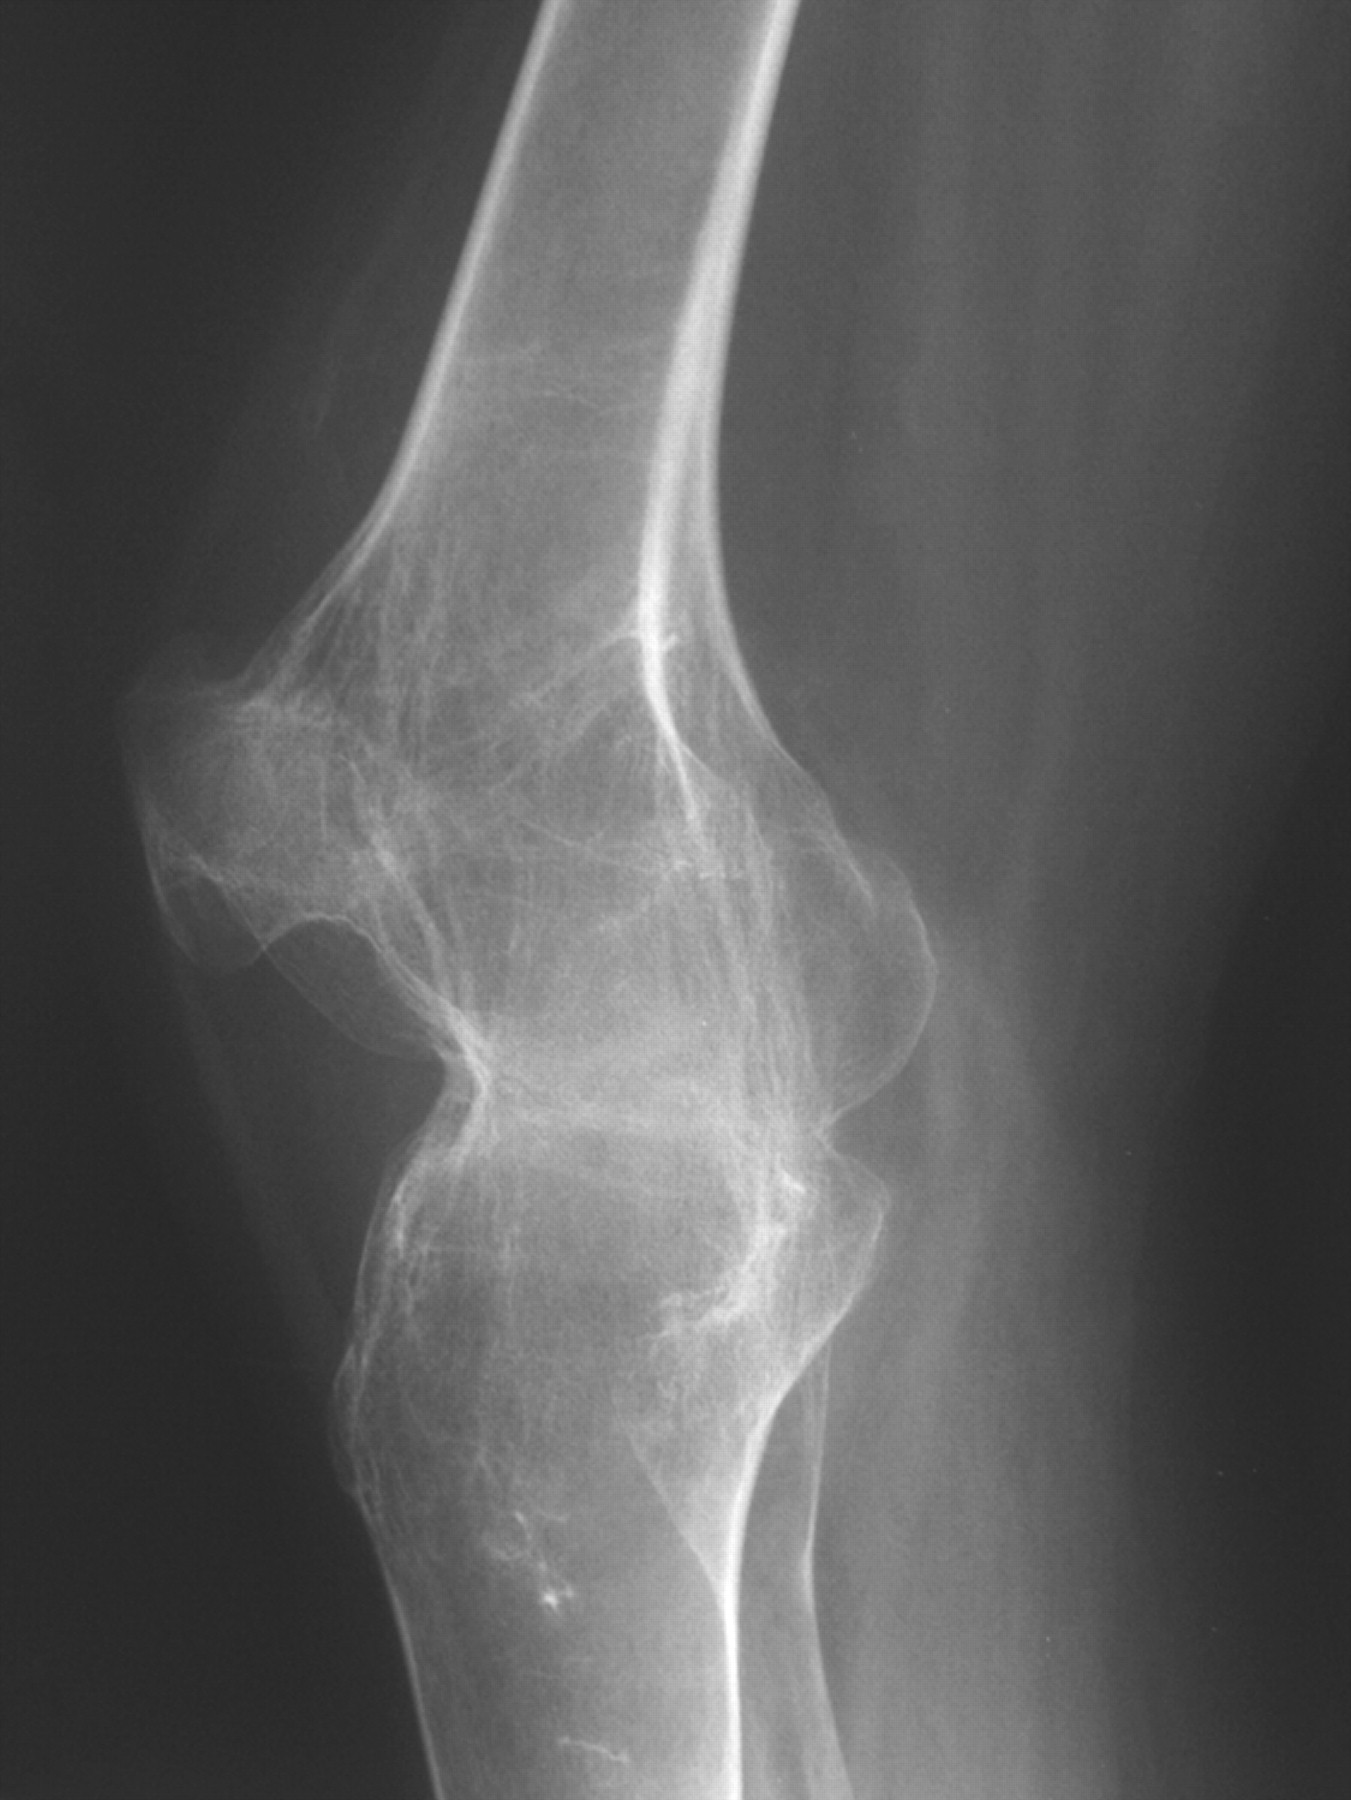

From radiopaedia.org

Ankylosis of the knee joint Image Ankylosis Dip Joint Arthritis of the dip and pip joints are very common forms of osteoarthritis seen in the hand and can be associated with pain and deformity. Arthrodesis of the distal interphalangeal (dip) joint is a reliable means of achieving pain relief in a symptomatic dip joint. Ankylosis is a condition in which condylar movement is restricted because of fusion of the. Ankylosis Dip Joint.